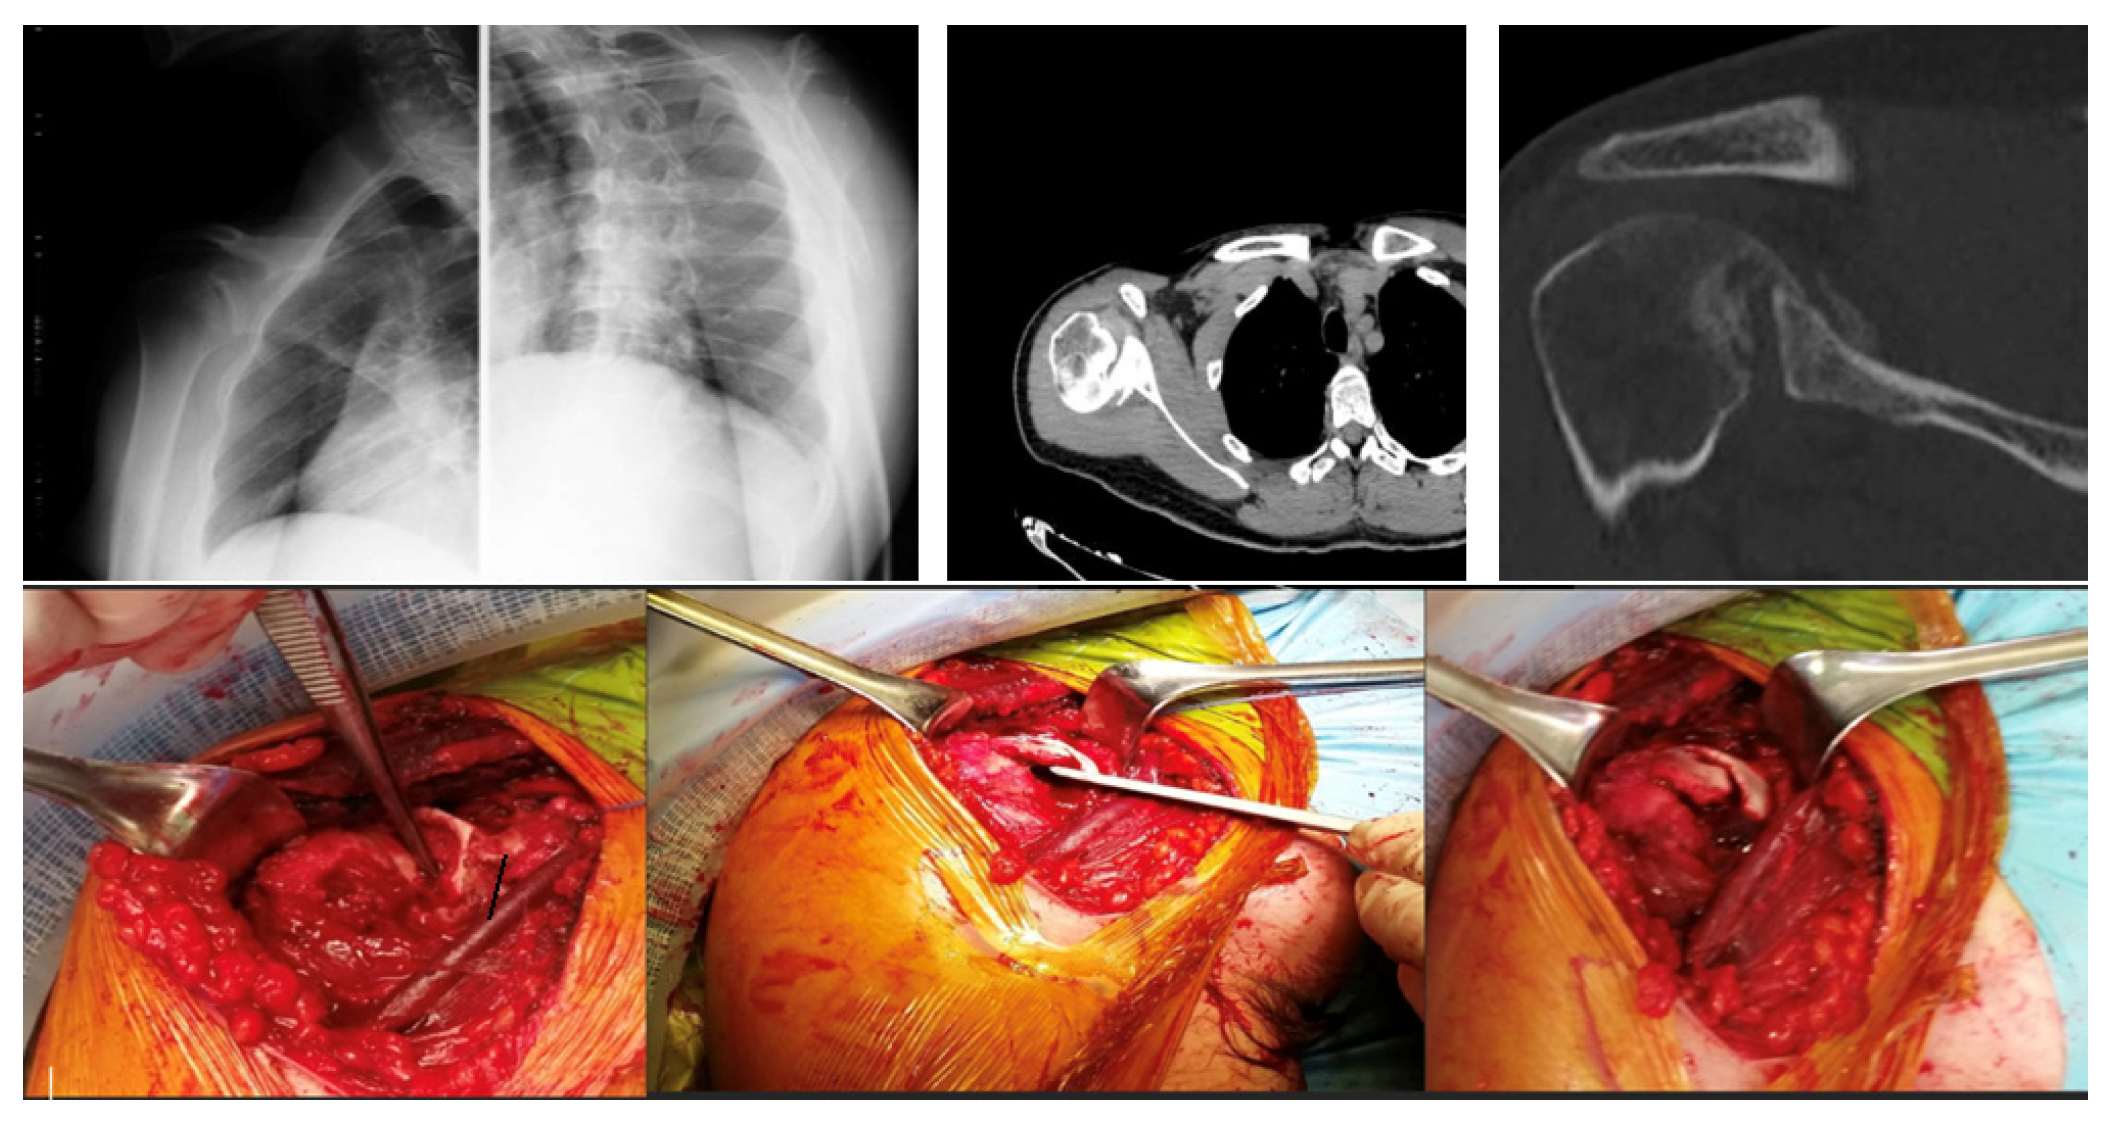

• Bone Grafting (Randelli Type 1): For Type 1 lesions with repairable impact injuries, particularly in younger patients and within a few weeks of trauma, bone grafting was performed. This involved detaching the subscapularis tendon, elevating the articular surface, and filling the defect. Bone grafting was specifically employed in cases classified as Randelli Type 1, characterized by a bone loss ranging from 20% to 50% of the humeral head articular surface. In all such instances, femoral head allografts sourced from a tissue bank were utilized. These allografts underwent precise intraoperative shaping to achieve an accurate press-fit within the humeral head defect. Fixation was then achieved using cannulated screws with washers, carefully positioned to ensure the screw heads were completely recessed and flush with the articular surface, thereby preventing any impingement. The rationale for selecting large, structural allografts from a tissue bank was based on the substantial dimensions and specific anatomical contouring required for effective reconstruction of these defects. Our unit benefits from a consistent supply of bone tissues, updated monthly through a collaboration with the Musculoskeletal Tissue Bank (BTM) of Bologna (Rizzoli Hospital), which ensured the ready availability of appropriate allografts for these procedures. The subscapularis tendon was then re-fixed in its original position with transosseous sutures (as illustrated in Figure 2 and Figure 3). The choice between synthetic grafts, cancellous allografts, or structural femoral-head allografts was based on lesion size and the quality of the residual humeral head bone stock.

In the 2 patients with repairable type 1 impact injury, in consideration of the time elapsed since the trauma of 3 weeks and their young age, the subscapularis tendon was first detached, then the articular surface was raised, filling the defect with cancellous allograft bone in 1 case and with synthetic bone in the other. Finally, the subscapularis tendon was fixed with transosseous suture in the original position (Figure 2).

The remaining 2 patients with type 1 injury 4 weeks after the trauma were treated by detachment of the subscapularis tendon, debridement of the humeral bone bed and the defect was filled with a structural wedge-shaped femoral head allograft fixed with 2 cannulated screws slightly sunk into the articular surface. Subsequently the tendon was sutured back to its original insertion (Figure 3).

Figure 2. A 28-year-old man diagnosed with type 1 injury 3 weeks after the trauma treated with reduction in the dislocation, detachment of the subscapularis, reduction in the articular surface, bore with spongy bank bone and suture in anatomical position with transosseous stitches of the tendon.

Figure 3. A 54-year-old man with type 1 injury 4 weeks after trauma. X-ray and clinical check-up at 12 months.